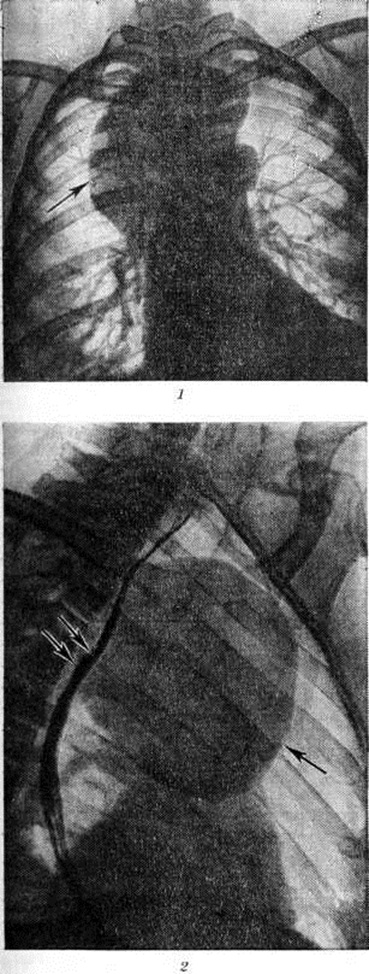

Рентгенологическое исследование (рентгеноскопия, рентгенография, томография и другие специальные методики) представляет надёжный способ выявления Дермоид. С помощью рентгенографии обнаруживаются углубления и дефекты в костях черепа, обусловленные истончением кости от давления Дермоид Контуры дефекта гладки и чётки, с уплотнённой каймой по краю. Дермоид пресакрального пространства могут обусловить краевой дефект передней

стенки крестца и отклонение копчика кзади. При расположении Дермоид в средостении наиболее полную информацию даёт пневмомедиастинография (смотри полный свод знаний) в сочетании с томографией (смотри полный свод знаний). Дермоид обычно представляется в виде однородной овоидной тени в верхнем или среднем отделе средостения (рисунок 2). Латеральные его контуры, выступающие чаще в правое лёгочное поле, обычно гладки или слегка волнисты; медиальные сливаются с тенью средостения, а при больших Дермоид они могут выступать и слева от него. Нередко отмечается обызвествление стенки Дермоид, могут обнаруживаться костные включения, зубы. В отличие от целомических и паразитарных кист конфигурация Дермоид не меняется в зависимости от дыхания и натуживания.

Отсутствует активная пульсация стенки. В распознавании Дермоид брюшной и тазовой полостей помогает Пневморетроперитонеум (смотри полный свод знаний) и пневмоперитонеум (смотри полный свод знаний).